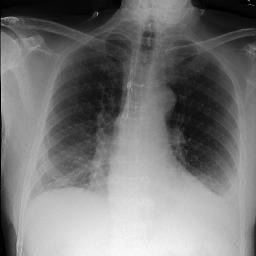

To address these issues, we propose a novel Adaptive patch-word Matching (AdaMatch) model to correlate chest X-ray (CXR) image regions with words in medical reports and apply it to CXR-report generation to provide explainability for the generation process. AdaMatch exploits the fine-grained relation between adaptive patches and words to provide explanations of specific image regions with corresponding words. To capture the abnormal regions of varying sizes and positions, we introduce the Adaptive Patch extraction (AdaPatch) module to acquire the adaptive patches for these regions adaptively. In order to provide explicit explainability for CXR-report generation task, we propose an AdaMatch-based bidirectional large language model for Cyclic CXR-report generation (AdaMatch-Cyclic). It employs the AdaMatch to obtain the keywords for CXR images and `keypatches' for medical reports as hints to guide CXR-report generation. Extensive experiments on two publicly available CXR datasets prove the effectiveness of our method and its superior performance to existing methods.